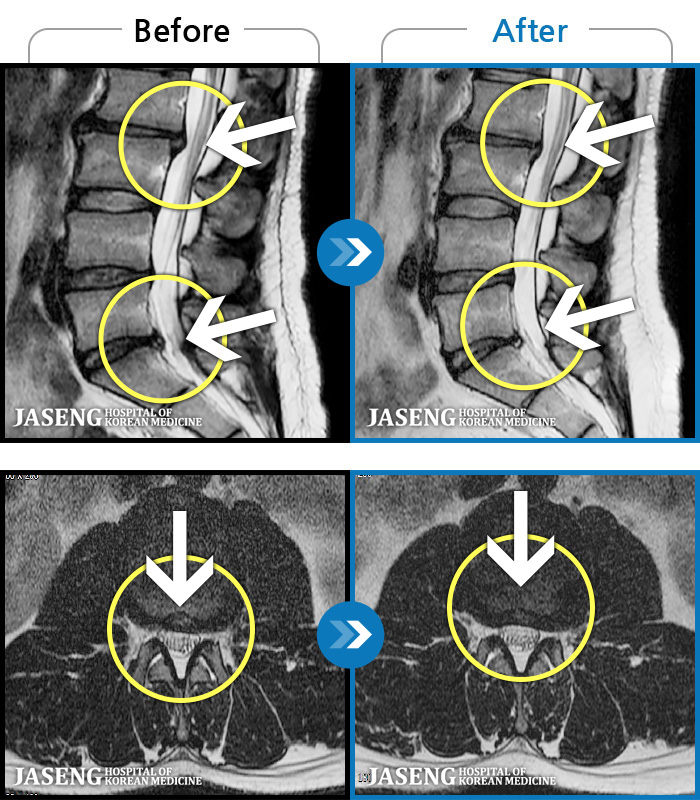

MRI ġ

56 MRI ũ ʸ Ȯϼ.